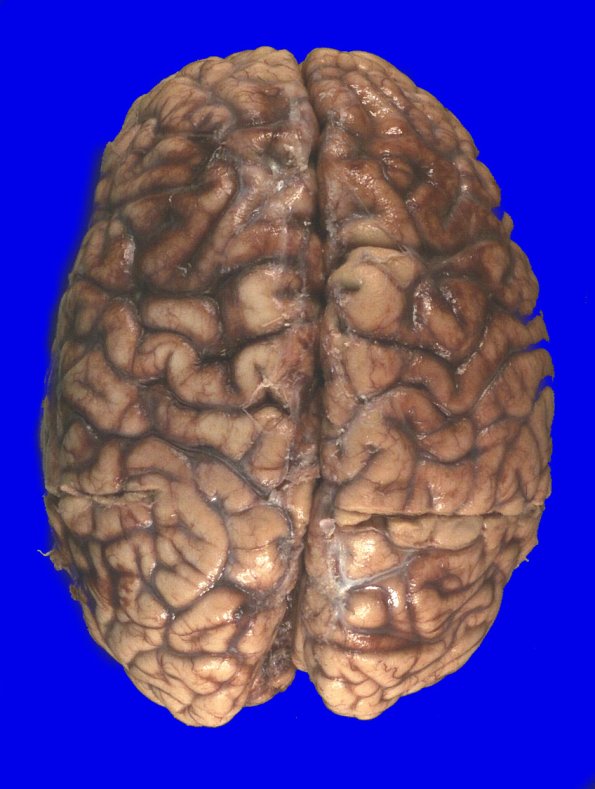

2E1,2 At autopsy the fresh brain weighed 1160g. There was mild atrophy of the cerebral hemispheres with mild atrophy of the cerebellum seen in the ventral view.